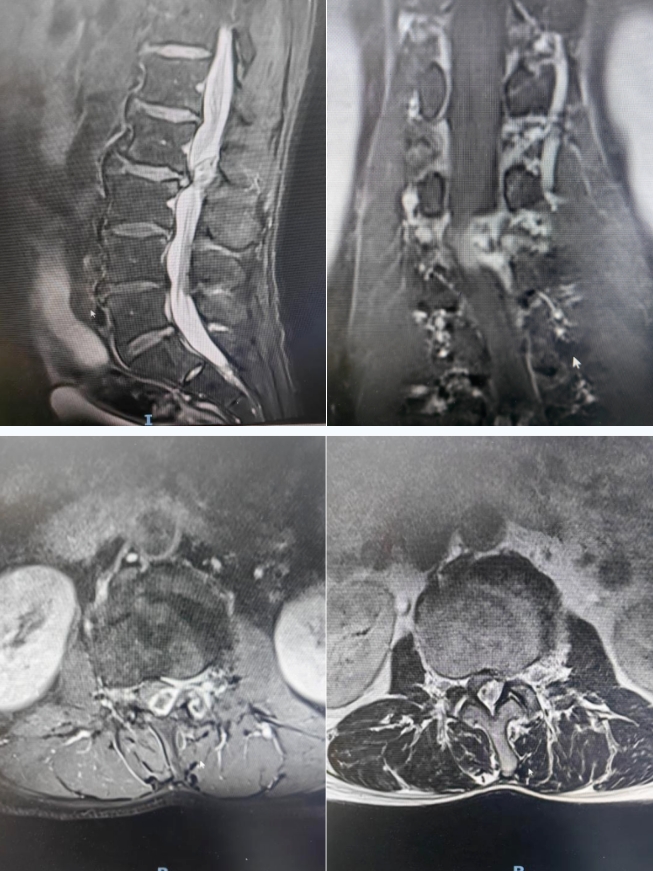

56岁男性患者,其腰部病痛史长达10年之久。早在10年前,劳动后便出现腰部困痛不适,且疼痛向双侧臀部放射,当时未重视。此后的10年间,每当从事重体力劳动或长时间行走,都会疼痛不已,却始终未接受正规诊治。直至10天前,患者在劳动后腰痛及臀部放射痛症状急剧恶化,甚至连正常行走都难以维持,休息后也无明显缓解,患者来到延安市中医医院(北京大学第三医院延安分院)寻求专业治疗。经门诊腰椎MRI检查显示,腰2-3椎间盘膨出并偏左型突出,同水平椎管后部存在占位,考虑为髓核游离或肿瘤性病变,同时继发椎管明显狭窄,随后以“椎管内占位性病变”收入脑外科。

患者入院后,腰椎MRI增强检查明确:腰2-3水平椎管内髓外硬膜外背侧偏左有环形强化结节,高度怀疑为髓核游离,并继发同层面椎管狭窄。脑外科迅速组织病例讨论,患者症状持续加重,日常生活严重受限,神经受压情况显著且有恶化趋势。为使患者恢复正常生活与工作能力,建议尽快实施手术治疗。在与患者及家属充分沟通并完善术前各项检查后,由脑外科主任田德洲操刀,在科室医师张晨等团队以及麻醉手术科的全力配合下,顺利为患者施行腰2-3椎管内占位切除术。术中发现,患者腰部肌肉存在陈旧性损伤,组织结构紊乱、层次不清,且伴有腰3椎体滑脱。为避免患者承受二次手术的痛苦,紧急邀请骨科专家会诊并联合手术,征得患者及家属同意后,为患者实施了腰3椎体滑脱椎弓根螺钉内固定植骨融合术以及椎板切除减压椎间盘切除术。手术过程顺利,经过医护团队的精心护理,患者恢复状况良好,腰背部及臀部疼痛症状完全消失,行走自如。出院时,患者感激地说道:“完全不疼了,心里的石头也终于落了地,终于能睡个安稳觉了,太感谢你们了!”